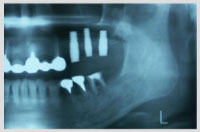

症例4 上顎奥歯 サイナスリフトを伴う症例2 年齢56歳 女性

初診時の状況

・左右上の奥歯がないのですが義歯は絶対に使いたくない

・以前大学病院で診察してもらったが10から12ヶ月の期間と3かいから4回の手術をしなければな

らないことと、手術料が大変高額でしたので断念した

・左上奥歯(エックス線写真では右の上となります)が終わったら右上もインプラントをしたい